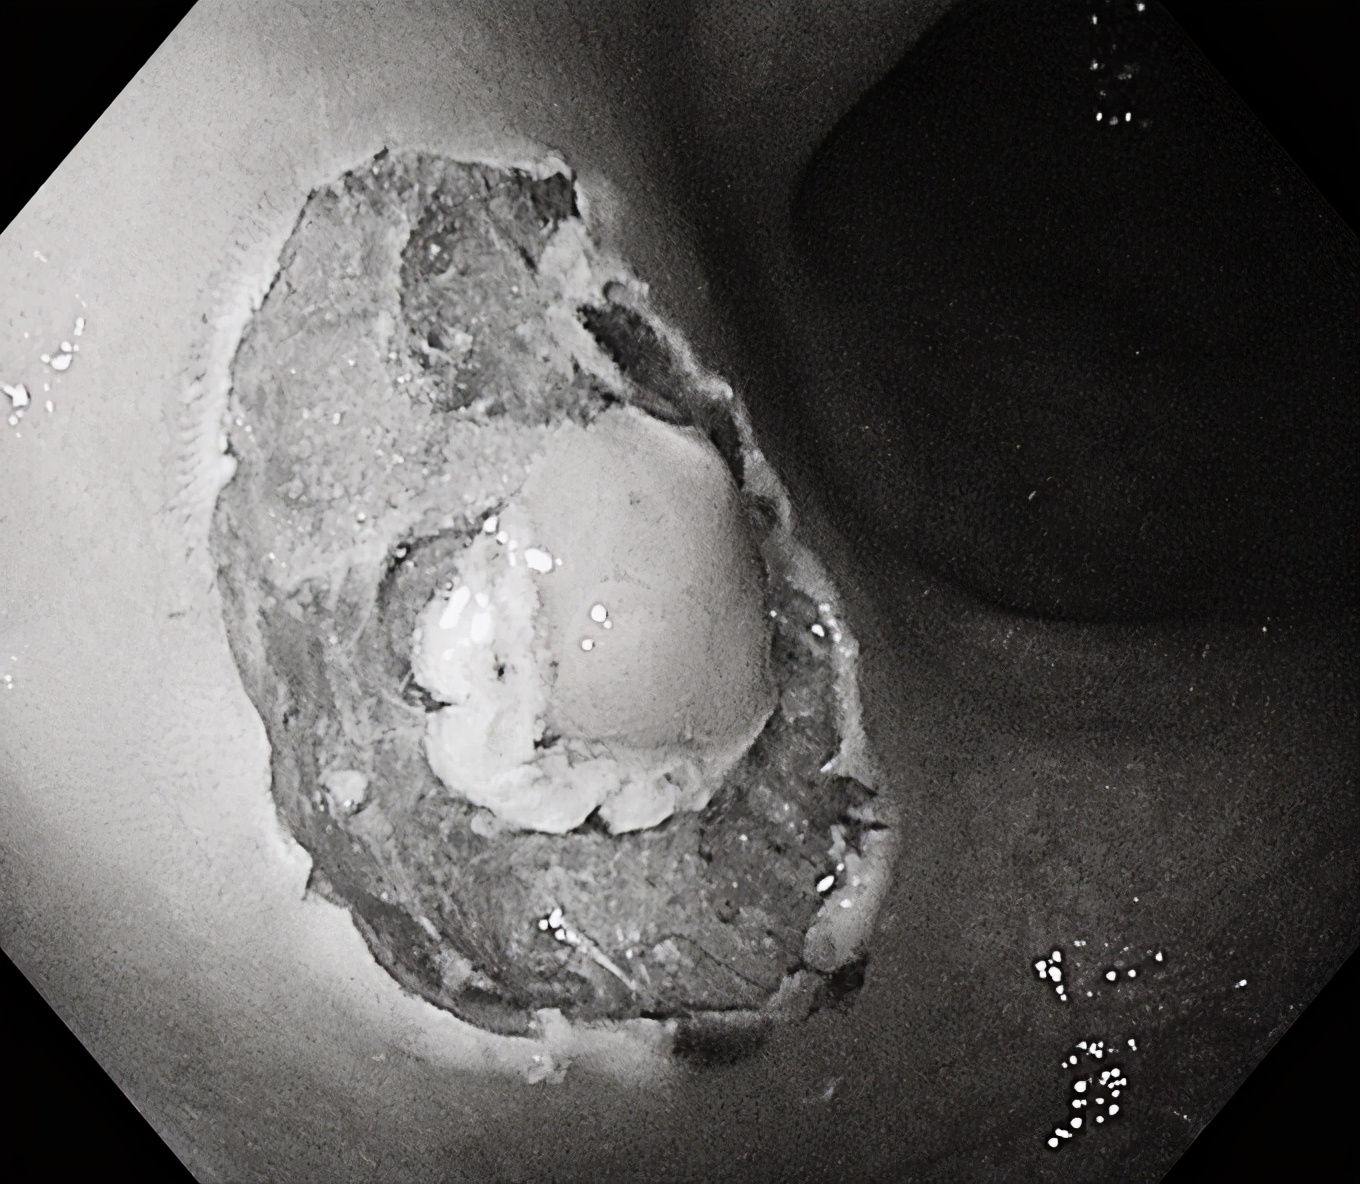

在随后一例肠镜检查中,一名中年女性患者结肠发现3枚无蒂锯齿状病变(SSL),该病变为结肠镜下极易漏诊的结肠癌癌前病变,我们用黄金刀成功施以内镜下黏膜剥离术(ESD)及内镜下黏膜切除术(EMR),完整切除结肠病变,根除了结肠癌的隐患!耗时仅仅10分钟左右,术后无并发症出现,同时送病理检查。

内镜粘膜下剥离术(Endoscopic submucosal dissection,ESD),是近年来临床对消化道早癌及较大侧向发育肿物的一项新的治疗手段,也是临床应用前景很好的技术,让更多的早期消化道癌能够在内镜下一次性完全切除,免除了器官切除等开腹手术的痛苦。ESD与剖腹手术及以往EMR等内镜治疗方法比较,具有以下优点:

④对于面积较大且形态不规则或合并溃疡、瘢痕的肿瘤进行96%以上的切除率,以减小复发概率。

对消化道早癌、巨大平坦息肉、粘膜下肿瘤(局限于黏膜肌层或黏膜下层的脂肪瘤、间质瘤、类癌等)可以应用ESD做到治愈性切除。